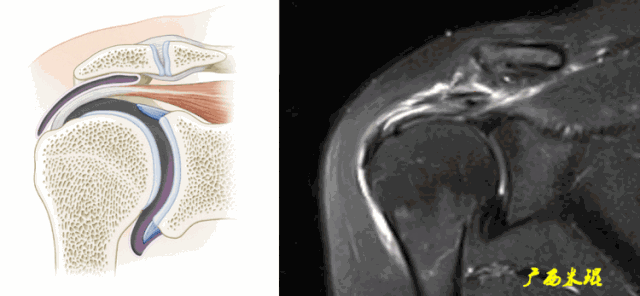

(2)肩峰下滑囊炎

肩峰下滑囊是一个非常重要的解剖结构,大部分肩关节的病变都会波及,肩袖损伤更不例外,同时,肩峰下滑囊炎的病变也可以波及到肩袖等组织。肩峰下滑囊炎在MRI上表现是非常明显的,如果其正常,肩袖一般也正常。

(3)肱二头肌长头腱病变

肱二头肌长头腱与肩袖关系极为密切,其肌腱炎、肌腱滑脱等改变很多情况下是伴随肩袖损伤而来的。当我们在MRI上发现肱二头肌长头腱的严重病变,应该也要考虑到有肩袖损伤的可能。

(3)邻近组织异常

邻近组织异常包括信号异常和形态异常,是肩袖撕裂的间接征象,对诊断有意义但不能直接诊断肩袖撕裂。邻近组织包括肩峰下滑囊、骨(肩峰、大结节、小结节、喙突)、关节(肩锁关节、盂肱关节)、肱二头肌长头腱等。

a.肩峰下滑囊增大,是肩袖损伤必有的表现。

b.肩峰下滑囊贯通(与关节腔相通),预示着肩袖的完全撕裂。